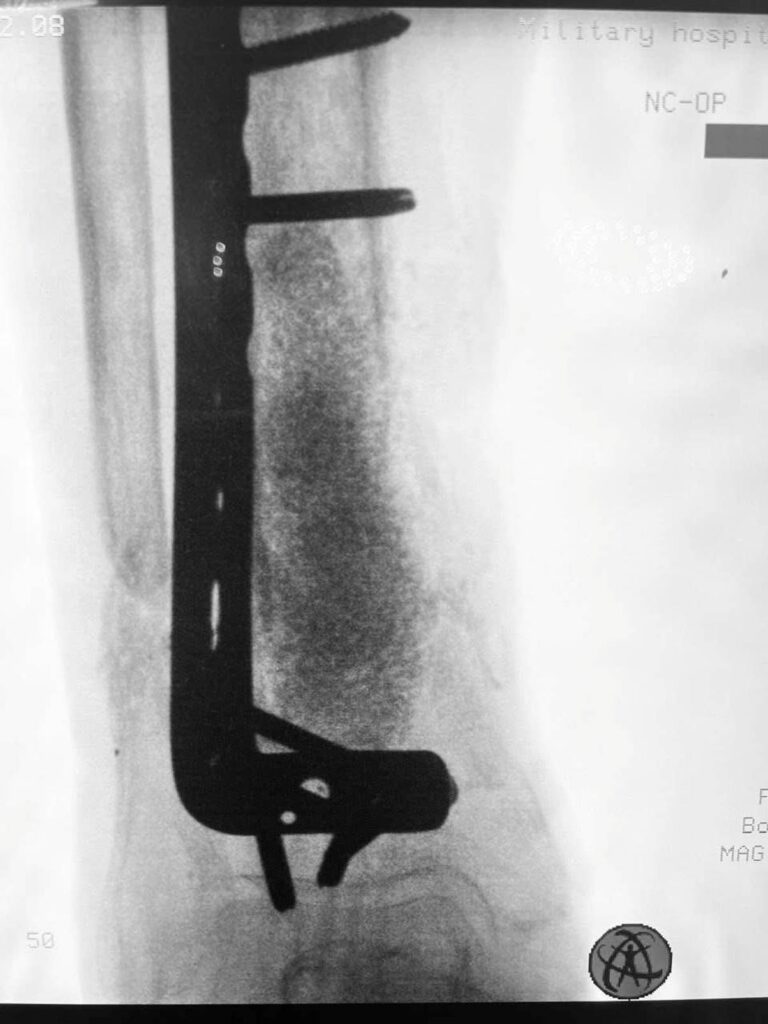

Минно-взрывное ранение военнослужащий (сейчас демобилизованный) получил в феврале этого года. Сначала выполнено 6 операций, направленных на первый этап сохранения руки (аппарат внешней фиксации и «чистки раны»). Несмотря на то, что в ране поселилась «военная» бактерия (американские хирурги называют её и еще одну – ацинетобактер – «иракская бактерия» или «болезнь ветеранов»), украинским врачам удалось с инфекцией справиться.

Поэтому вместе с фиксацией этой реально разрушенной плечевой кости (см рентгенограмму) пластиной из минидоступов, мы с Vasyl Parii и Денисом Долгушем не стали одномоментно делать и массивную костную пластику. Взяли ткани снова на посев. Если посев будет стерилен, то следующим этапом сделаем пластику. Если нет, – то вновь проведем антибактериальную мощную терапию.